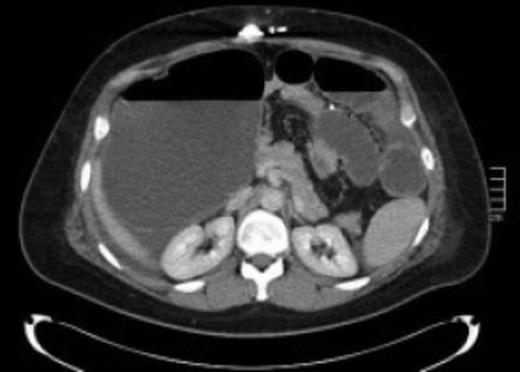

In May 2011, a 36-year-old woman presented with a 3-day history of vomiting, diarrhoea, abdominal distension and colicky pain. Medical history included laparoscopic adjustable gastric banding fitted in May, 2007, for class III obesity, when her body mass index (BMI) was 45.7 kg/m2. She underwent two band fills in 2008 and her BMI, thirteen months post-gastric banding, came down to 28.9 kg/m2. She subsequently underwent abdominoplasty and breast reduction in 2009. On examination, her BMI was 31.0 kg/m2, blood pressure 119/84 mmHg, pulse rate 109 per min and temperature 36.1oC. She had peri-umbilical tenderness but no guarding or signs of peritonitis. She had leucocytosis 15.8 x109 with neutrophilia 14.14×109 and her CRP was 19 mg/L. Abdominal ultrasound showed grossly dilated ascending colon (maximum diameter 11.5 cm) with multiple fluid filled loops of small bowel indicating intestinal obstruction. A CT scan revealed caecal volvulus with a distended caecum of at least 19cm in diameter (see Figure 1).

Axial Computed Tomography scan of abdomen demonstrating distended bowel